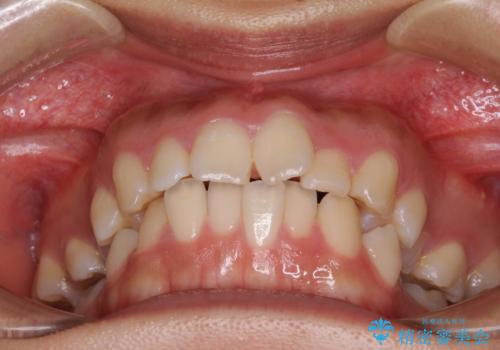

- 咬み合わせと口元の突出感を気にして来院された患者様です。

上顎に対して、下顎が後方にある咬み合わせであるため、上顎左右小臼歯のみの抜歯か、下顎左右小臼歯も抜歯とするのか悩むところでした。

まずは上顎のみ抜歯を行って矯正治療を進め、下顎小臼歯も抜歯が必要となれば速やかに抜歯することとしました。